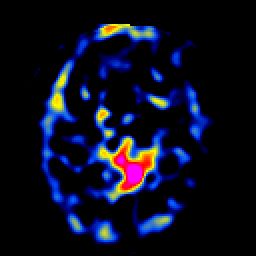

SPECT TL Study #5 -- Slice #30